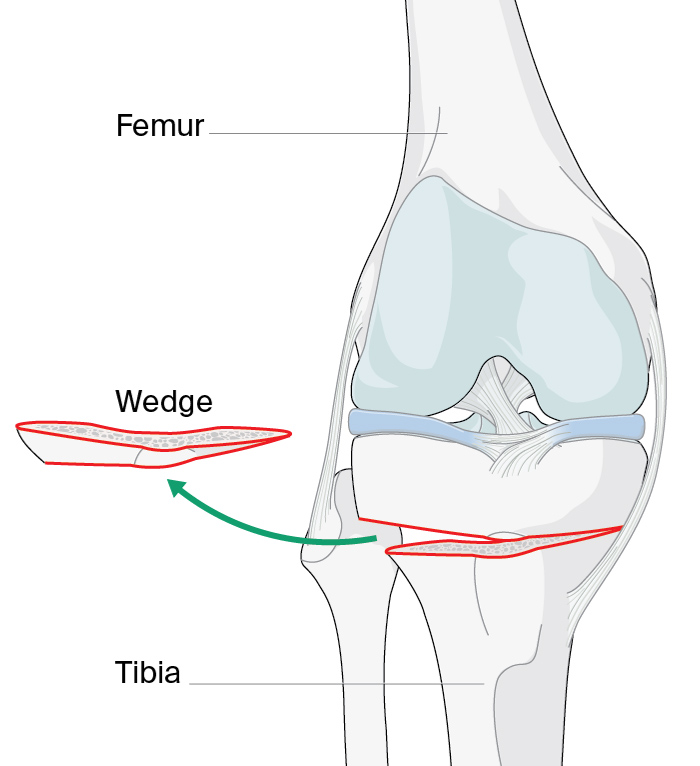

Figure 2. Arrows indicate the load distribution before (left) and after (center) the procedure (medial open wedge osteotomy with locked plate osteosynthesis)(right). Used under CC BY-SA 3.0 de license. Source. Image (right) by J Lengerke.

A wedge-shaped cut (see Figure 1) is made in the top of the tibia to change the alignment of the knee by shifting the weight/loading of the arthritic part of the joint to the healthier part (see Figure 2) [12]. It is mostly performed for varus deformities, less commonly for valgus deformities [13]. Preoperative planning using imaging helps surgeons to calculate the size of the wedge/osteotomy needed to correct the weight-bearing axis (see Figure 3). For best results, it is critical that correct alignment is achieved [14]. There is controversy around what constitutes the ideal mechanical alignment but generally the recommended alignment range is between 2° and 6° of mechanical valgus [15].